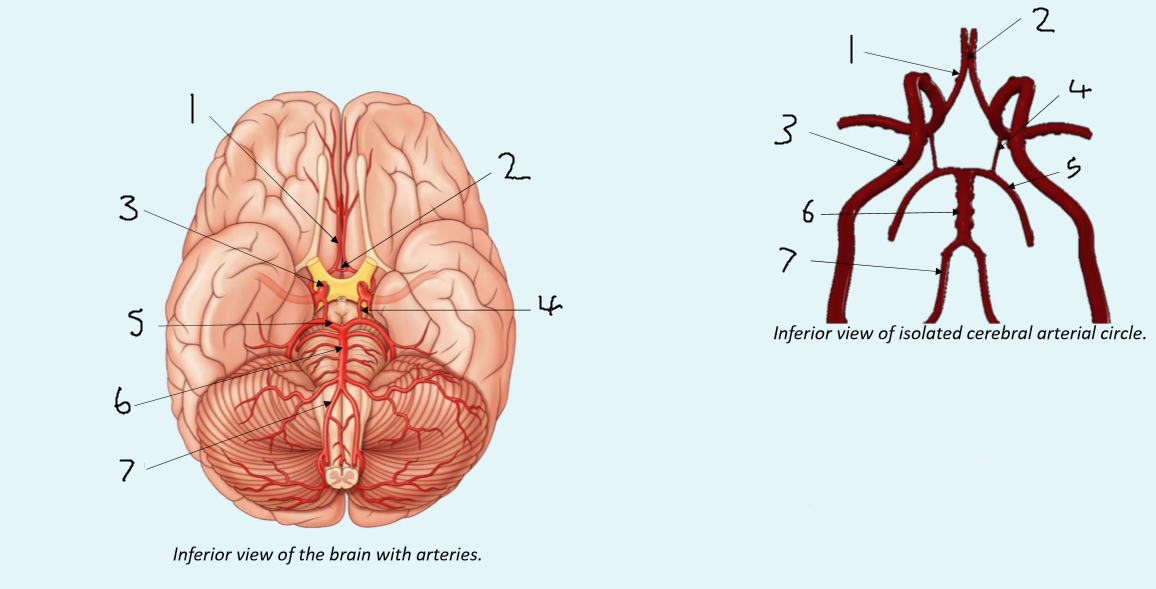

What is 1?

anterior cerebral artery

What is 2?

anterior communicating artery

What is 3?

internal carotid artery

What is 4?

posterior communicating artery

What is 5?

posterior cerebral artery

What is 6?

basilar artery

What is 7?

vertebral artery

What is 1?

anterior communicating artery

What is 2?

anterior cerebral artery

What is 3?

middle cerebral artery

What is 4?

internal carotid artery

What is 5?

posterior communicating artery

What is 6?

posterior cerebral artery

What is 7?

superior cerebellar artery